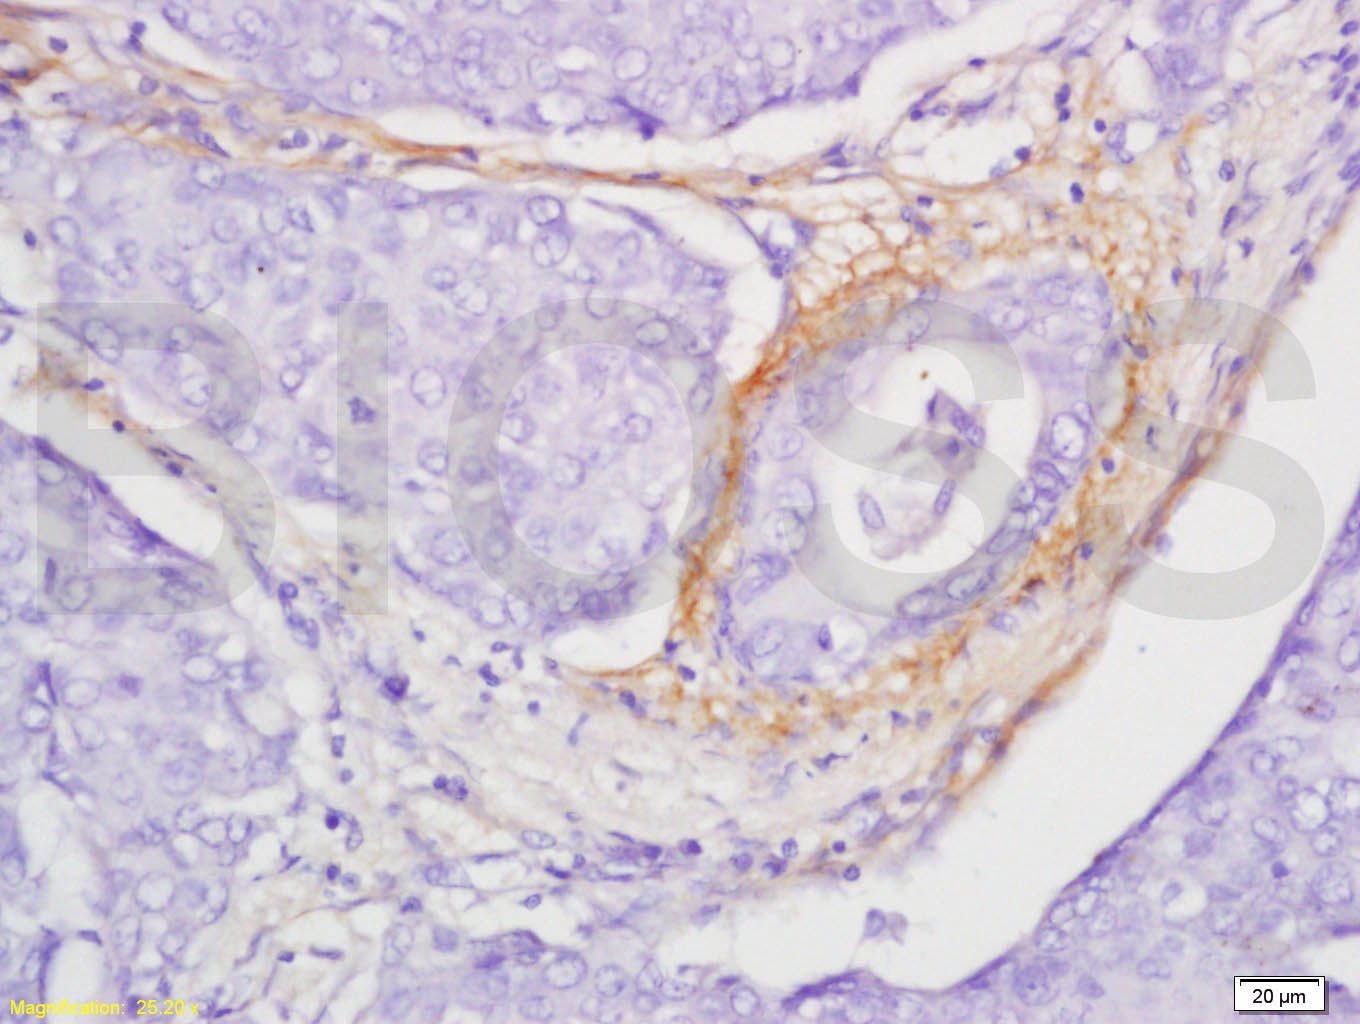

Paraformaldehyde-fixed, paraffin embedded (Rat testis); Antigen retrieval by boiling in sodium citrate buffer (pH6.0) for 15min; Block endogenous peroxidase by 3% hydrogen peroxide for 20 minutes; Blocking buffer (normal goat serum) at 37°C for 30min; Antibody incubation with (CCL4) Polyclonal Antibody, Unconjugated (bs-1046R) at 1:400 overnight at 4°C, followed by operating according to SP Kit(Rabbit) (sp-0023) instructions and DAB staining.